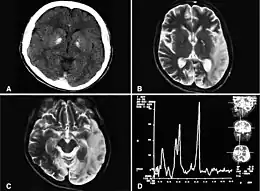

Description de l'image A computed tomography brain scan showing bilateral basal ganglia calcification.jpg.

les lésions cérébrales ne sont pas de topographie vasculaire et sont plus souvent postérieures qu'antérieures[5].